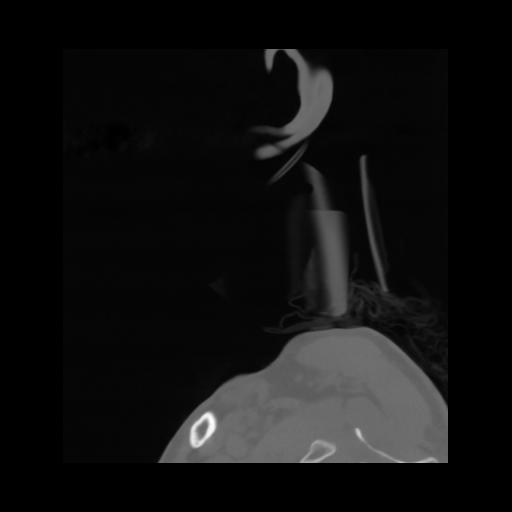

14 P.BLANDAS,,Sagittal,2.000,P.BLANDAS,Sagittal,